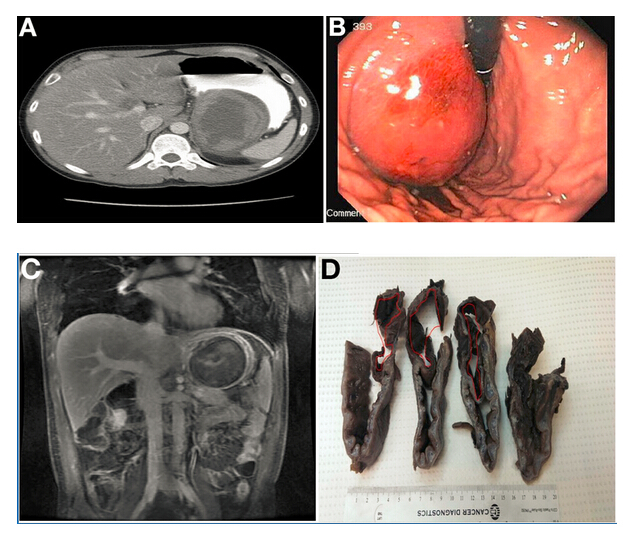

腹部計(jì)算機(jī)斷層掃描(CT)顯示胃底有一9.8×7.4cm不均質(zhì)腫塊(圖A),在隨后的胃鏡檢查中也發(fā)現(xiàn)該腫塊(圖B)。

腹部磁共振成像(MRI)進(jìn)一步明確為界限清楚、不均質(zhì)腫塊,對(duì)比增強(qiáng)(圖C),提高了對(duì)胃腸道間質(zhì)瘤(GIST)的懷疑。計(jì)劃手術(shù)切除。

術(shù)中發(fā)現(xiàn)可疑病變具有定義不明的外科平面和顯著的周圍纖維化,最終行空腸食管Roux-en-y吻合術(shù)。組織學(xué)檢查(圖D)和顯微鏡標(biāo)本(圖E)顯示正確診斷。

令人驚訝的是,胃大部切除標(biāo)本(圖D)檢查發(fā)現(xiàn)在疑似腫瘤的胃壁區(qū)域內(nèi)有扁平囊。這一扁平囊可以拉伸到9×8×4.5cm。胃囊與真實(shí)胃腔之間有一處共同的壁。通過(guò)此壁的組織學(xué)切片(圖E)顯示了分隔壁兩側(cè)的平滑肌細(xì)胞層和胃黏膜。這排除了GIST,證實(shí)胃重復(fù)畸形的診斷(GDC)。胃重復(fù)畸形是一種罕見(jiàn)的先天性異常,僅占胃腸道所有重復(fù)囊腫的4%至9%。大多數(shù)病例報(bào)告發(fā)生在兒童中且位于胃大彎處。GDC有以下3個(gè)特點(diǎn):(1)囊腫的壁與胃壁相連,(2)囊腫由平滑肌包圍,通過(guò)肌肉與胃壁相連,(3)囊壁排列有胃上皮或其它類型的胃黏膜。